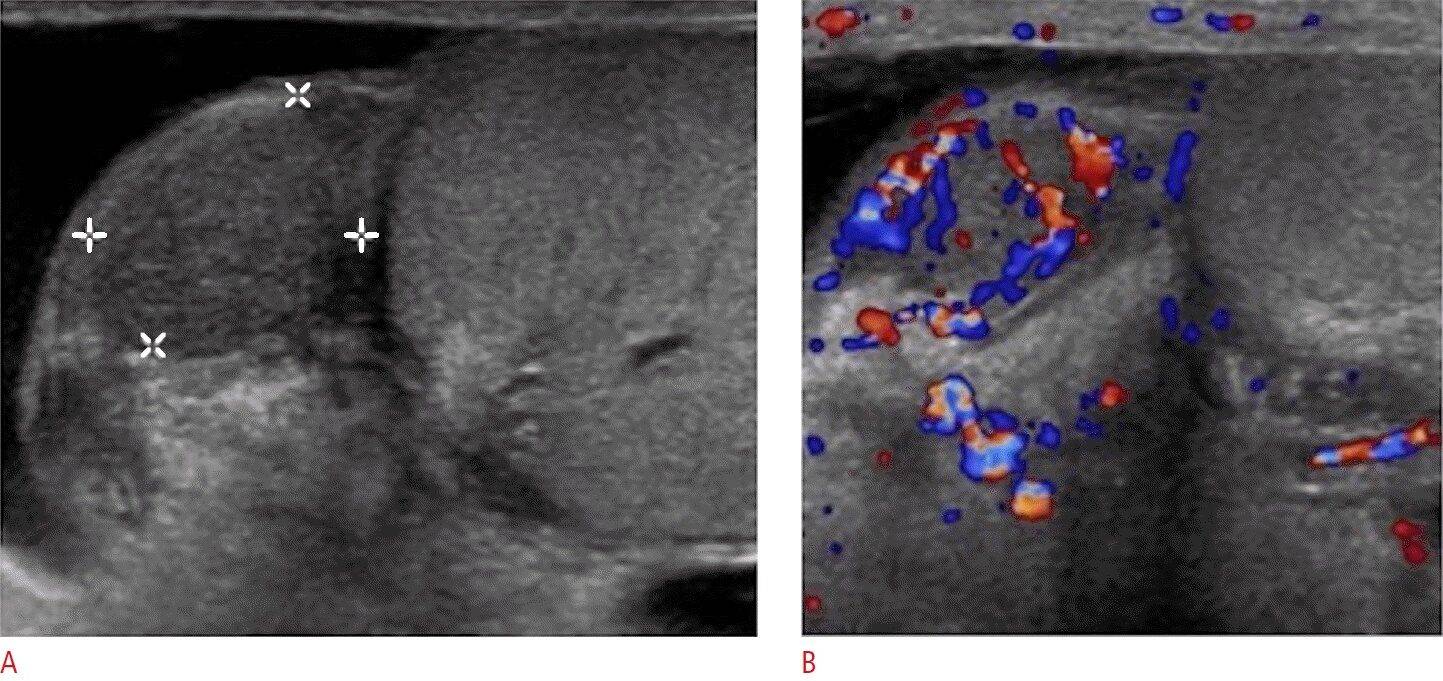

При обследовании применяют ультразвуковую диагностику, осмотру подвергаются все органы, расположенные в брюшной полости. Данный способ обследования позволяет исключить/подтвердить наличие метастазов во внутренних органах мужчины. Также можно качественно обследовать лимфатические узлы и органы, которые находятся за пределами брюшной полости на предмет наличия/отсутствия в них метастазов.

Большую важность имеет ультразвуковое обследование самого яичка, ведь оно позволяет иногда обнаружить связующие элементы между образовавшейся опухолью и новообразованиями в мошонке. Пациенту часто предлагают сделать рентгенографию легких. Такой вид обследования может показать есть либо нет в легких метастазы.

Опухоль яичка, операция

Первая операция, которая будет проведена даже при подозрении на опухоль яичка еще до лечения и установления полного диагноза – это биопсия яичка . Она относится к малоинвазивным операциям и в большинстве случаев сводится к проколу опухоли специальной иглой для забора ткани опухоли под контролем ультразвукового аппарата.

С ее помощью врач сможет точно установить опухоль это или нет, тип опухоли, злокачественная опухоль или доброкачественная, из какой ткани она произрастает, степень злокачественности, является опухоль первичной или метастазом опухоли из другого органа, которая себя никак не проявила (например, если была опухоль печени, она метастазировала, образовалась опухоль левого яичка у мужчин, лечение будет уже направлено на совершенно другой тип опухоли). В зависимости от данных, полученных с помощью биопсии, будет строится дальнейшая тактика лечения.